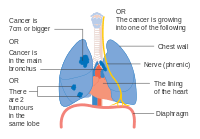

- Diagrams of main features of staging

One option for stage IIB lung cancer, with T2b; but if tumor is within 2 cm of the carina, this is stage 3 Stage IIIA lung cancer

Stage IIIA lung cancer Stage IIIA lung cancer, if there is one feature from the list on each side

Stage IIIA lung cancer, if there is one feature from the list on each side Stage IIIA lung cancer

Stage IIIA lung cancer Stage IIIB lung cancer

Stage IIIB lung cancer Stage IIIB lung cancer